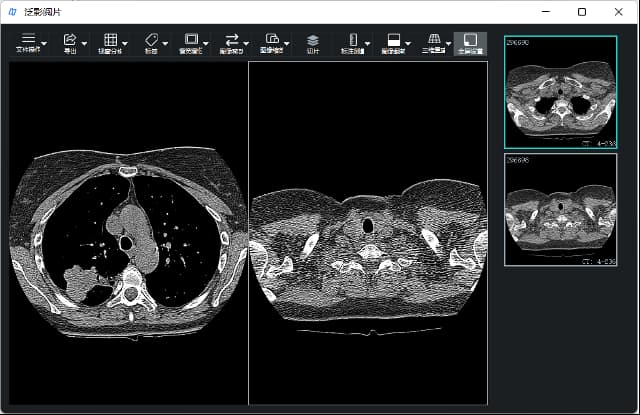

打开图像序列,即打开指定文件夹下的图像序列,打开后可用右侧导航栏翻阅序列,如下图所示。

二宫格显示。以两个宫格方式显示2张图像,如下图所示。